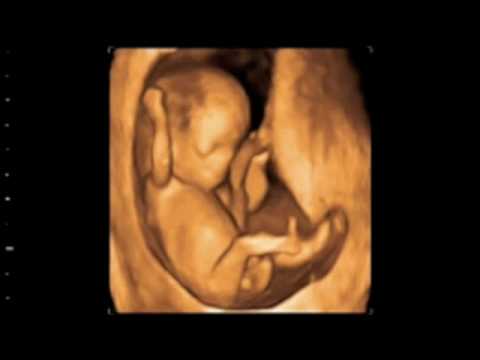

Faszinierende Ultraschallbilder

Ultraschallbilder bieten faszinierende Einblicke in

verschiedene Stadien

des Kindes im Mutterleib und veranschaulichen seine Entwicklung.

5. bis 9. Woche

6. Woche

8. Woche

11. Woche

12. Woche

13. Woche

28. Woche